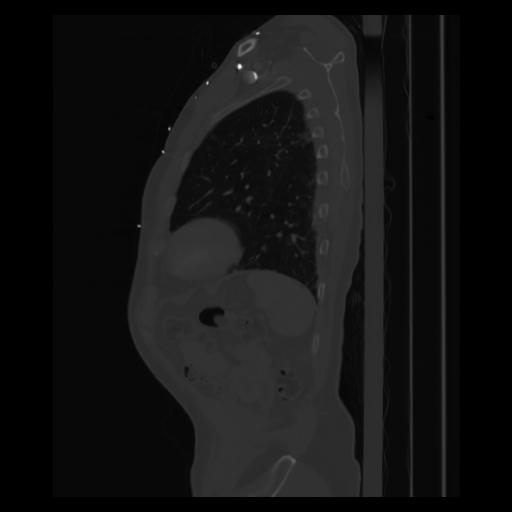

30 CUERPO,CE,Sagittal,3.000,CUERPO,Sagittal,